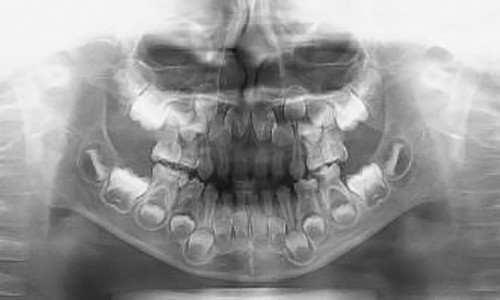

交換期のパノラマレントゲンの状態です

歯の高さが変わってゆきます

交換期には既存の乳歯と永久歯の歯の生えている高さに違いが出てきます。それまで通りの歯磨きをしていても、実は新しく生えてきた永久歯には歯ブラシが当たっていないことも多く、永久歯の初期虫歯を作ってしまう子がいます。交換期の歯並びには敏感になって下さい。特に下顎第一大臼歯は「6歳臼歯」と言われる通り6~7歳頃に生えてくることが多く、日本人の平均寿命からから考えると80年近く使っていかなくてはならない歯です。虫歯治療は初めが肝心です!是非、お子様の定期検診にはグランツ歯科クリニックにお越しください。